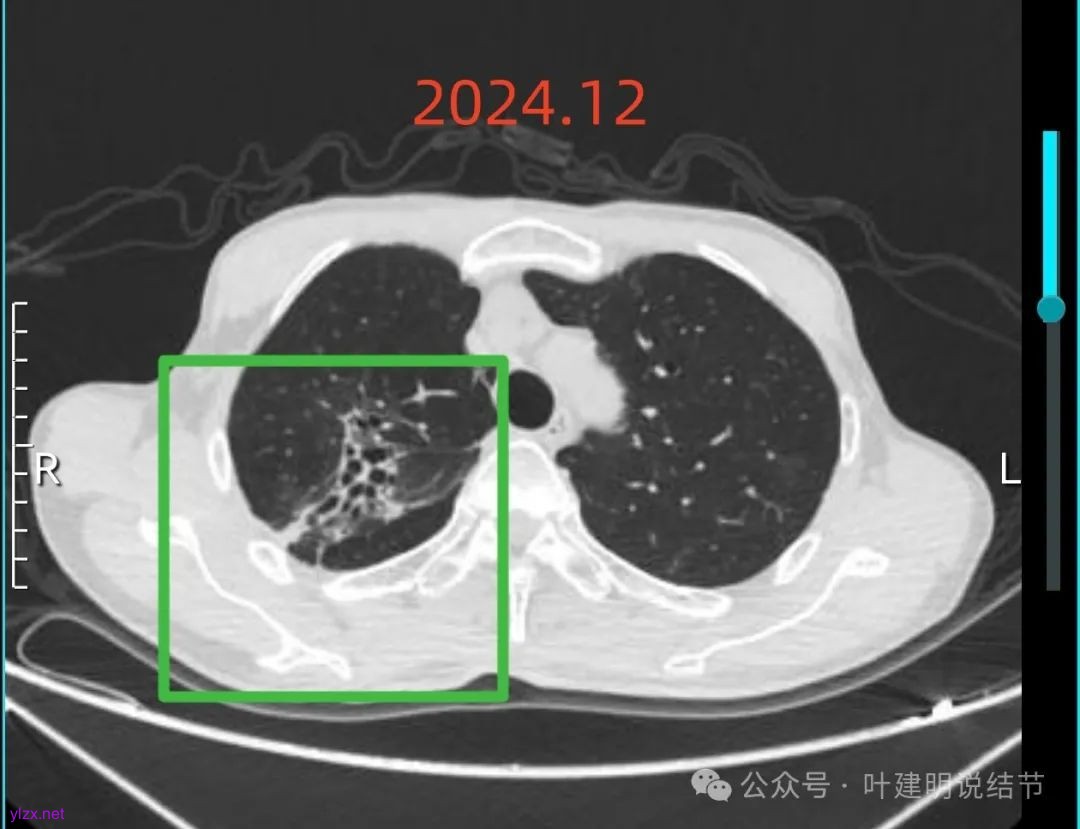

再来看2024年12月时的影像:

右上混合阴影也没有明显进展,则同样要更倾向确实是支气管扩张伴慢性炎与纤维增生的关系,可随访。

左上病灶血管进入了病灶且有异常增粗,边缘有淡的细毛刺的样子。

灶内血管明显,管壁略毛糙,有异常增粗,红色箭头处有点状高密度,边缘有毛刺征。

灶内出现了明显的实性成分,整体轮廓较清。

除了原血管进入外,另外角度也见到其他血管发出分支走向病灶,而且灶内密度不均,实性成分明显。